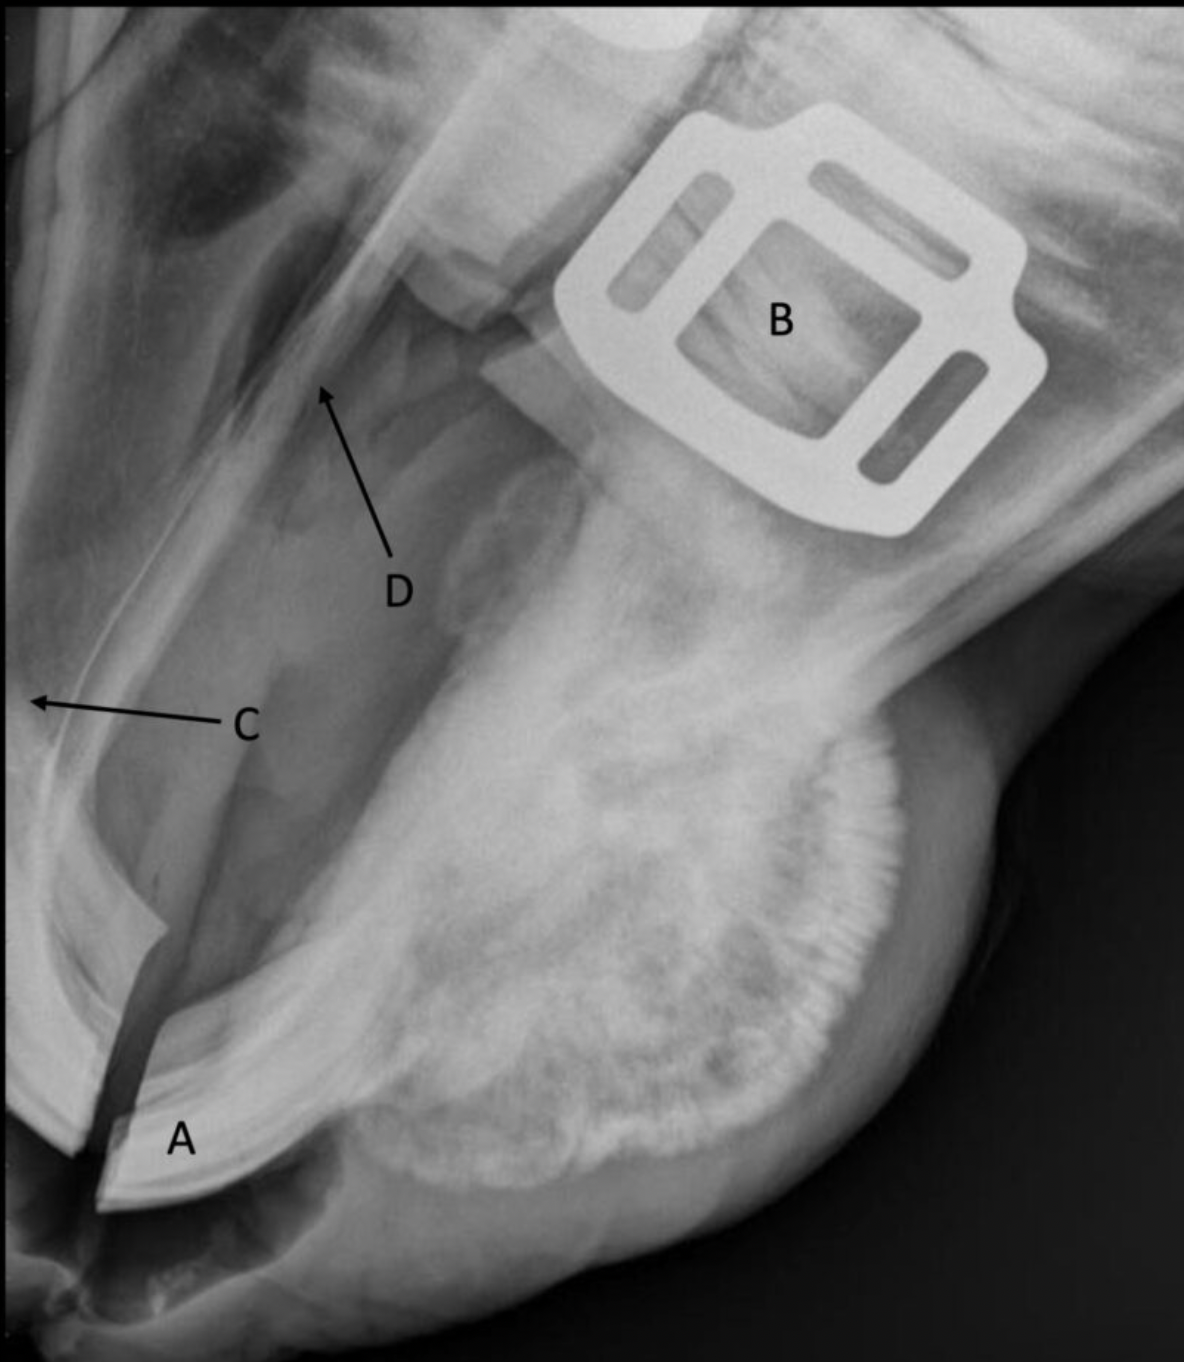

Label the structures

A

A = patella

B = distal femur

C = fabellae

D = tibia

E = fibula